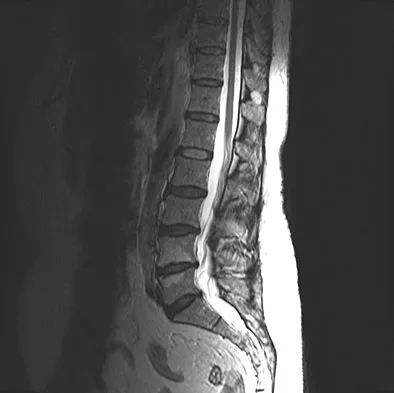

Question 37

A 37-year-old man with a history of congenital flatfoot reports worsening pain on the medial aspect of his ankle for the past year. The pain is worse with weight bearing and is better with rest and the use of an ankle brace. What findings are shown on the MRI scans shown in Figures 18a through 18c?